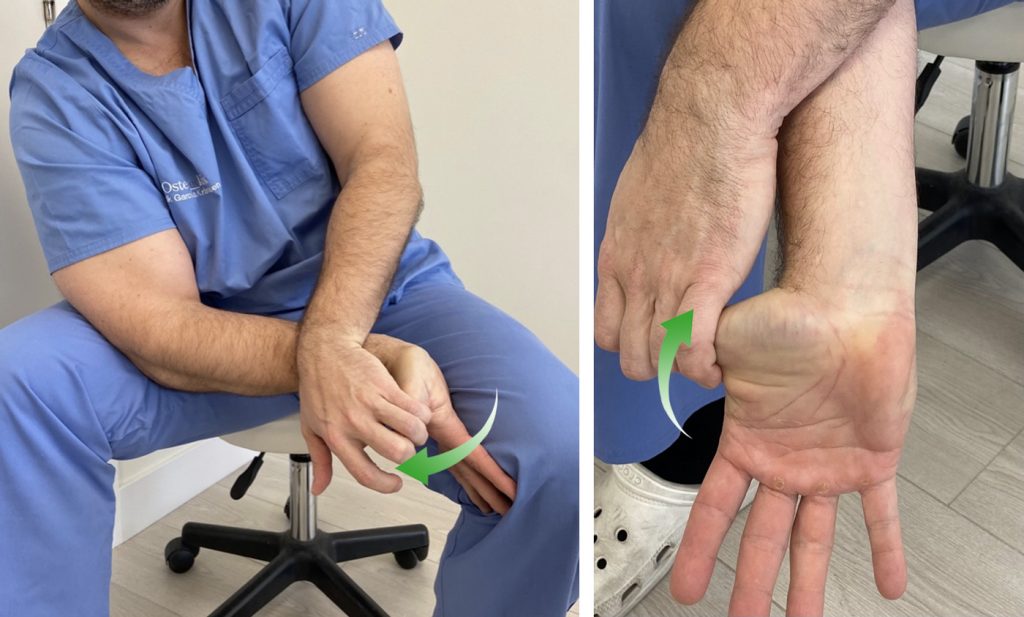

3. Nervio Cubital

Vamos a realizar, primero, una puesta en tensión y estiramiento del nervio para después pasar a una movilización.

Partimos de una posición erguida de pie o sentado.

Con el pulgar y el índice hacemos “pinza” describiendo un pequeño círculo.

Vamos a realizar una flexión del hombro elevando el codo, a la vez que hacemos flexión del codo y flexión dorsal de la muñeca como si quisiéramos colocarnos unos “anteojos”.

Muy probablemente no consigamos llegar hasta colocar la palma de la mano en nuestra cara. No importa, llegamos lo más cerca que podamos.

De esta manera estamos poniendo en tensión el nervio cubital y podemos sentir la sensación de tensión y cierto hormigueo en el brazo y la mano.

Para movilizar el nervio, vamos a repetir esta secuencia bajando el codo y estirándolo y haciendo flexión palmar de la muñeca. Y volviendo de nuevo a la posición de estiramiento.